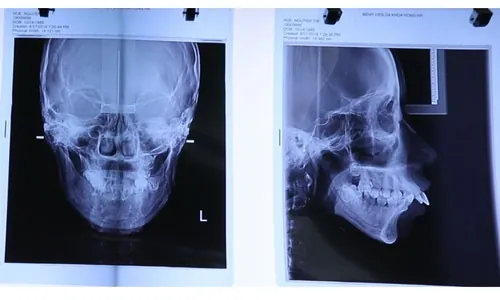

Nguyễn Thị Huê được thăm khám chuyên sâu, chụp xương cùng máy CT SCanner, bác sĩ chuyên khoa chỉnh hình hàm mặt nhận định đây là trường hợp KHÓ, PHỨC TẠP.

Thông qua hình ảnh chụp xương hàm mặt, bác sĩ có thể khẳng định phần tiền hàm trên hình thành quá phát, đẩy ra ngoài tới 3cm.

Do vậy, khớp cắn hai hàm lệch hoàn toàn ảnh hưởng trực tiếp tới sự cân đối khuôn mặt và chức năng ăn nhai của bạn Nguyễn Thị Huê.

Không chỉ khung xương hàm mà ngay phần trục răng cũng bị đẩy cong ngả ra phía trước. Điều này khiến phần miệng của Huê không thể đóng chặt lại.

Có thể thấy rõ, vùng môi trên luôn bị hở do toàn bộ thân răng bị lộ nằm phía ngoài khung hàm. Tình trạng này không thể chỉ đơn giản can thiệp niềng răng như các trường hợp vẩu thông thường.

➤ Thiểu sản vùng cằm, khuôn mặt teo lép

Vùng xương cằm thiếu hụt, ngắn lẹm so với tổng thể chiều dài khuôn mặt nên khi nhìn trực diện càng lộ rõ khuyết điểm hàm hô vẩu nặng.

Huê chụp xương bằng công nghệ 4.0 đánh giá tình trạng mức độ khuyết điểm hàm và răng